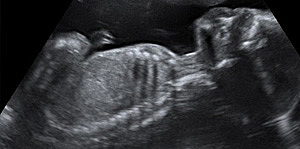

El latido del corazón del bebé se ve muy claro en la ecografía y su tubo neural ya empieza a cerrarse. De ahí la importancia de la suplementación de ácido fólico en el embarazo.El embrión ya mide entre 2 y 4 milímetros en la semana 6 de embarazo. Esta medida es la longitud desde la cabeza (el polo cefálico) hasta el final de la columna vertebral (el polo caudal). Por eso a esta medida se le llama LCC, Los ojos se están formando así como el primer vestigio cerebral

Al principio de esta semana, el bebé mide unos 4 a 5 milímetros y al final de la misma ha doblado con creces su longitud hasta tener una longitud cráneocaudal (LCC o medida desde la cabeza al coxis) de 1,2 centímetros, Se están desarrollando los intestinos, Están empezando a aparecer los vestigios de las piernas y los brazos, El embrión sigue teniendo una cabeza muy grande en comparación con el resto del cuerpo y una extremidad opuesta en forma de pequeña cola curvada.

En la cara aparecen los párpados y comienza el desarrollo de la retina.Comienza a formarse la punta de la nariz y las orejas.En el corazón se diferencian las válvulas aórtica y pulmonar. El árbol bronquial se divide en múltiples bronquiolos, engrosándose el tronco principal.En los miembros, aparecen los codos y crecen en longitud las piernas y los brazos. Los brazos adoptan una forma curvada y se dibujan los surcos de los dedos de las cuatro extremidades.

El embrión mide entre 2 y 3 centímetros en la semana 9 de embarazo y su forma ya es mucho más parecida a un ser humano: Aparecen las manos con los dedos y las muñecas, Las piernas se alargan aparecen los pies con sus dedos correspondientes. La cabeza sigue siendo la parte más grande en proporción con el resto del cuerpo los párpados cubren parcialmente los ojos. Los pabellones auriculares están bien formados. La boca se aprecia e incluso se abre.

La longitud del embrión es de 3 a 4 centímetros y su peso, unos 5 gramos. Podemos determinar el peso del embrión. El embrión cada vez tiene más forma humana y se distingue los brazos y los antebrazos, así como las manos que se abren y se cierran y están a la altura de la boca. La cara es más redondeada. Los ojos permanecen cerrados y la boca se abre y se cierra. La mineralización de los huesos progresa intensamente, sobre todo en el cráneo.

La ecografía puede decirnos muchas cosas: si hay malformaciones graves, si falta alguna extremidad, o incluso adelantar el sexo del bebé, porque ya están formados los genitales externos. La embarazada suele entrar en una etapa de mayor estabilidad (menos náuseas y vómitos) a medida que su útero crece.La cabeza sigue ocupando la mitad de la longitud embrionaria. Aparecen barbilla y cuello a medida que la cabeza se va separando del pecho. Empiezan a diferenciarse las uñas de los dedos.

El peso del feto oscila entre 8 y 14 gramos y mide entre 5 y 6 centímetros desde la cabeza al coxis.Los huesos tienen unos centros de osificación que les permiten ir creciendo. Los dedos de manos y pies están separados unos de otros y tienen movimiento.